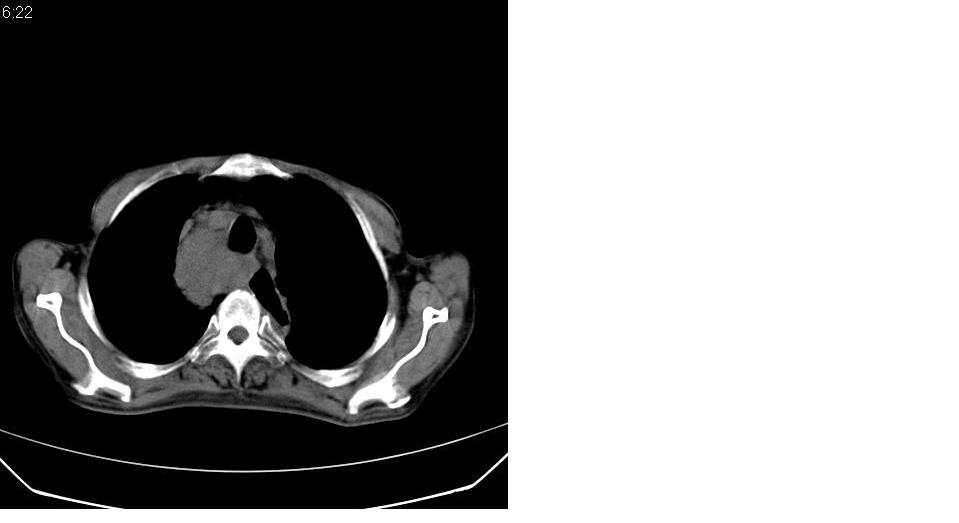

男 76岁,去年在外医院行食道癌手术,现胸闷,呼吸困难,肺窗有慢支肺气肿,无其它。

考虑----食管癌术后改变〔胃作食管重建术〕-------纵膈淋巴结转移

淋巴结转移,食道癌术后变胸腔胃。

纵隔淋巴结转移,纵隔术后改变、胸腔胃。

了解病史。支持纵隔淋巴结转移的诊断,但如果是上段食道癌术后就应考虑食道癌术后吻合口复发伴淋巴结转移。

上段食道癌术后,胸腔胃,术后吻合口复发伴淋巴结转移。